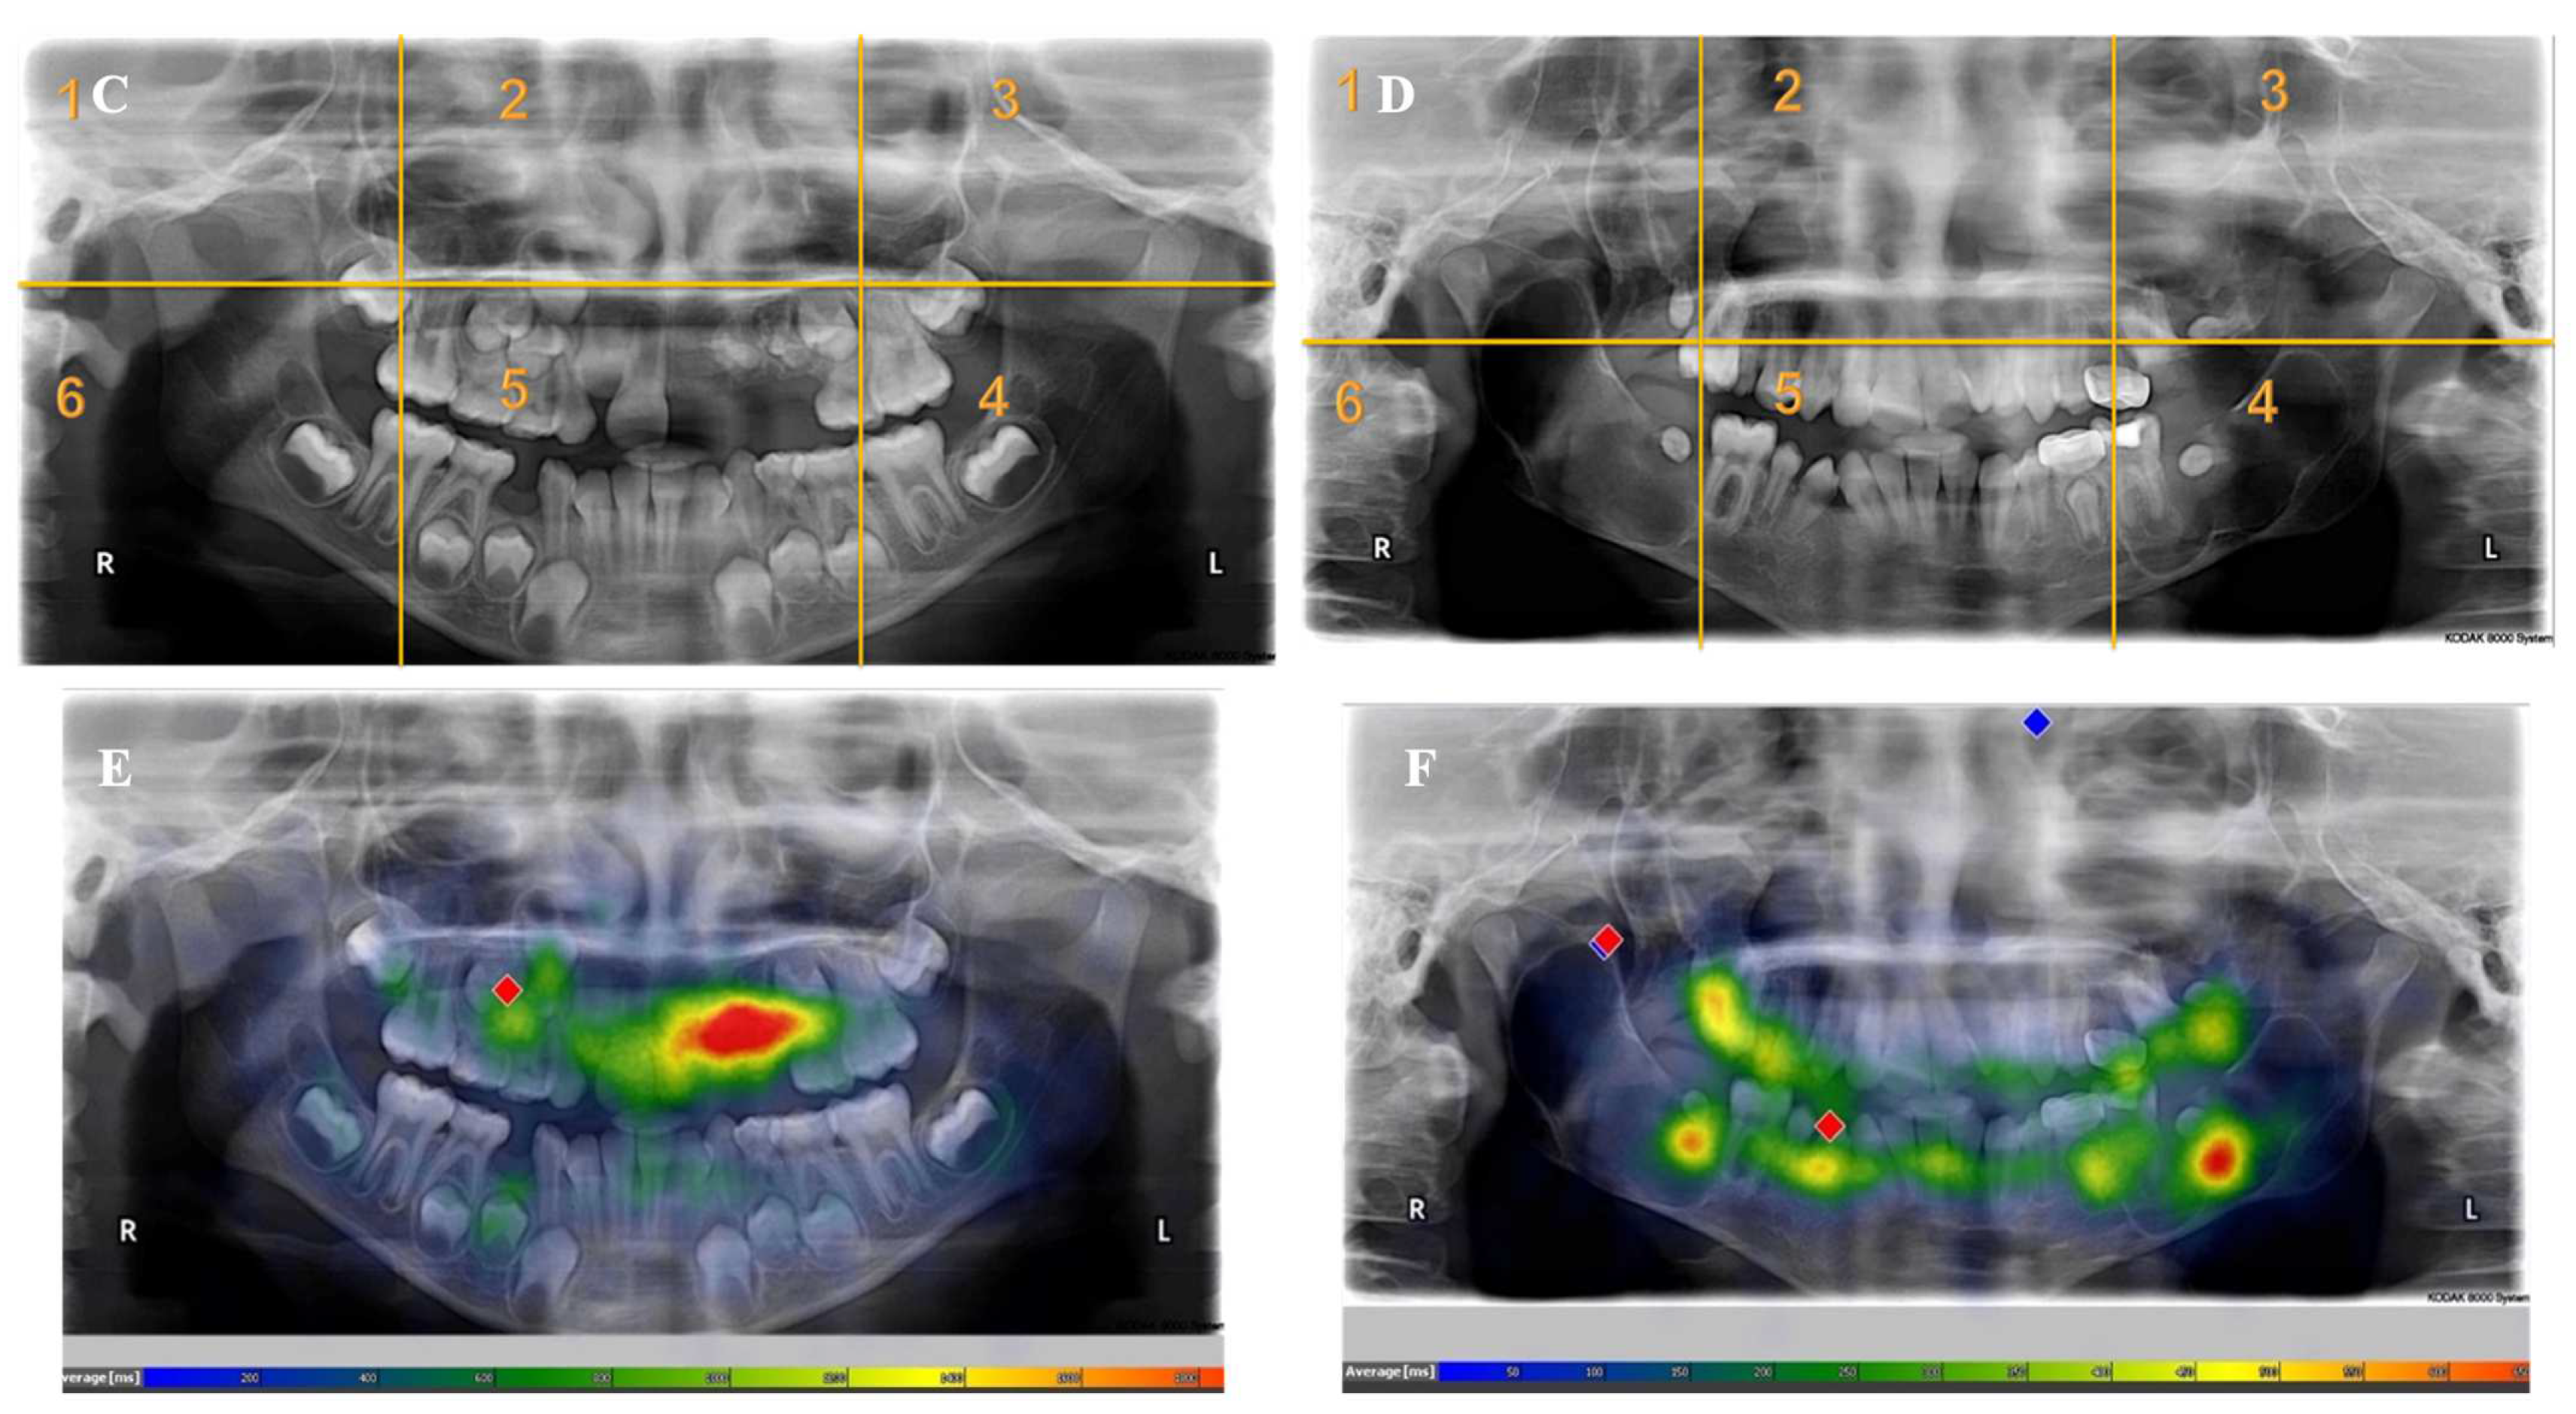

Appendix A. Radiographs Included in the Study

- Each panoramic radiograph displayed will be divided into sextants by yellow lines.

| Radiographs with Abnormalities | Number of Sextants Involved | Number of AOI a | Number of Participants | Total Recorded Observation b |

|---|---|---|---|---|

| Radiograph 1 | Multiple | 3 | 30 | 90 |

| Radiograph 2 | Multiple | 8 | 30 | 240 |

| Radiograph 3 | Single | 2 | 30 | 60 |

| Radiograph 4 | Single | 2 | 30 | 60 |

| Radiograph 5 | Single | 1 | 30 | 30 |

| Radiograph 6 | Single | 1 | 30 | 30 |

| Radiograph 7 | Single | 1 | 30 | 30 |

| Overall Observations | 540 |

| Revisit Count (Frequency Count) | 4 (1–8) | 5 (3–10) | 2 (0.5–5) | 7.338 [<0.001] |

| Fixation Count (Frequency Count) | 4 (0–11) | 9 (4–20) | 1 (0–6) | 10.273 [<0.001] |

| Entry Time (Milliseconds) | 3551.9 (1073.3–11,721.4) | 2878 (941.4–11,062.7) | 4000.1 (1227–13,907.25) | −1.918 [0.055] |

| Fixation Time (Milliseconds) | 1389.15 (0–3591.9) | 2736.8 (1335–6040.6) | 550.7 (0–2269.3) | 9.740 [<0.001] |

| Dwell Time (Milliseconds) | 1414.15 (0–3696.35) | 2820.35 (1335–6207.5) | 550.7 (0–2286.1) | 9.782 [<0.001] |